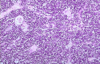

What does the box in this picture indicate?

GALT -> AKA Peyers patches

Where is this tissue found?

Small intestine